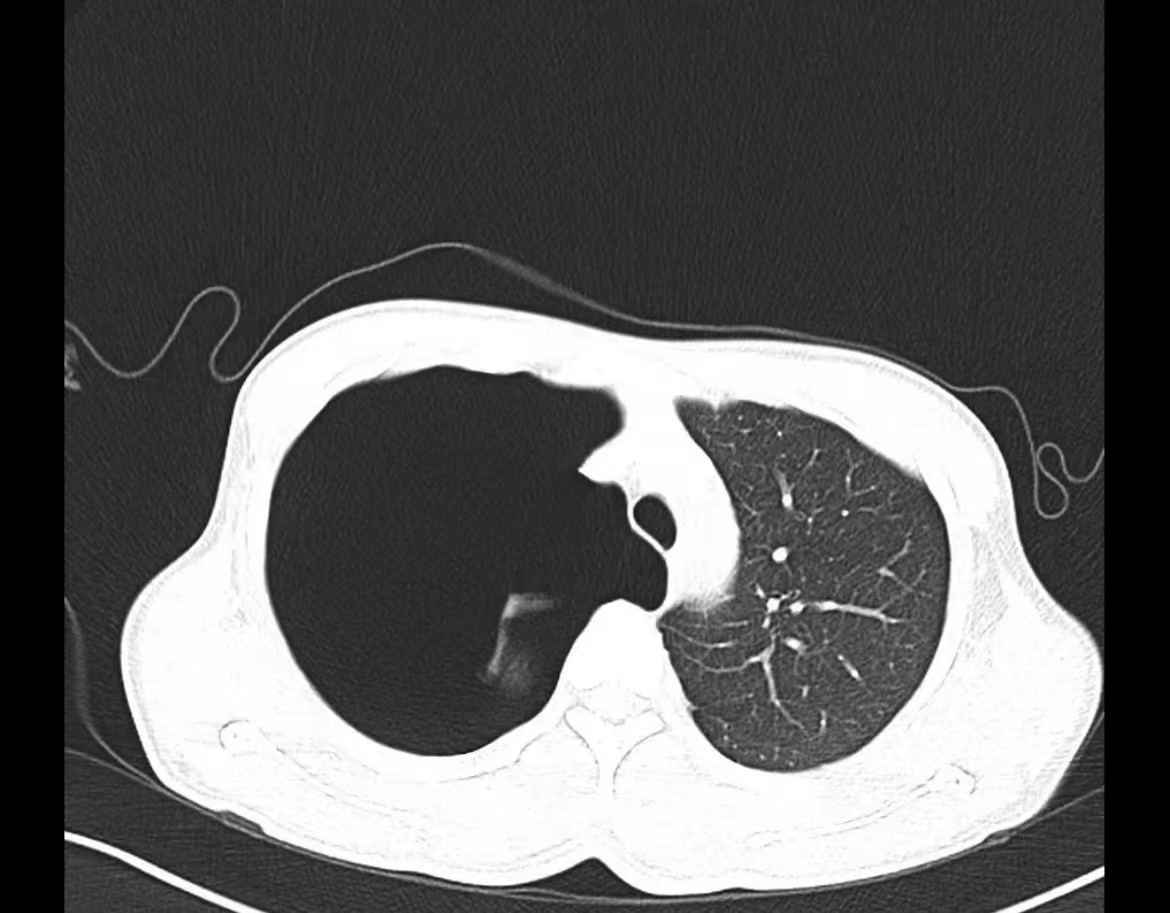

夜班急诊来了一位老大娘,捂着胸口来到CT室说:“医生,快帮我检查一下吧,看我出了什么毛病,胸口痛得厉害,出气都可疼,还闷得慌!”。于是立马登记完检查信息、赶紧给她进行CT扫描,结果一看是气胸,图像如下:

老大娘下了扫描床便说:“都怪我家那儿子,30好几了还不结婚,还没说他两句还给我顶嘴,给我气得直哆嗦,然后我就开始这样了”。看来肺还真能被“气炸”了啊!